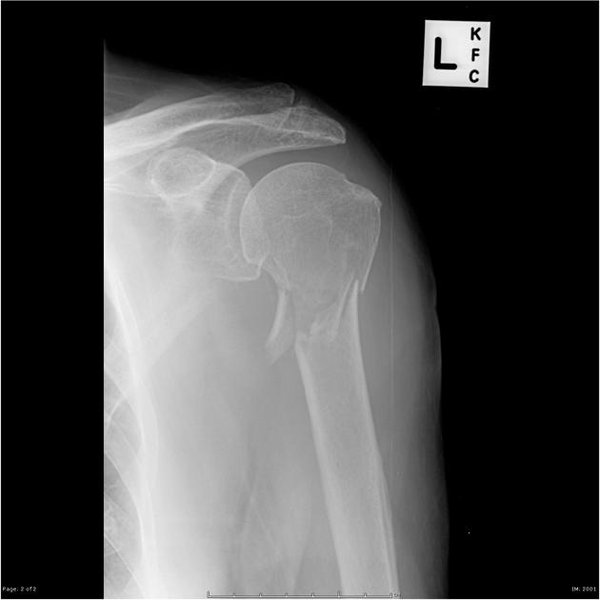

X-ray of a Proximal Humerus Fracture

An X-ray illustrating a proximal humerus fracture.